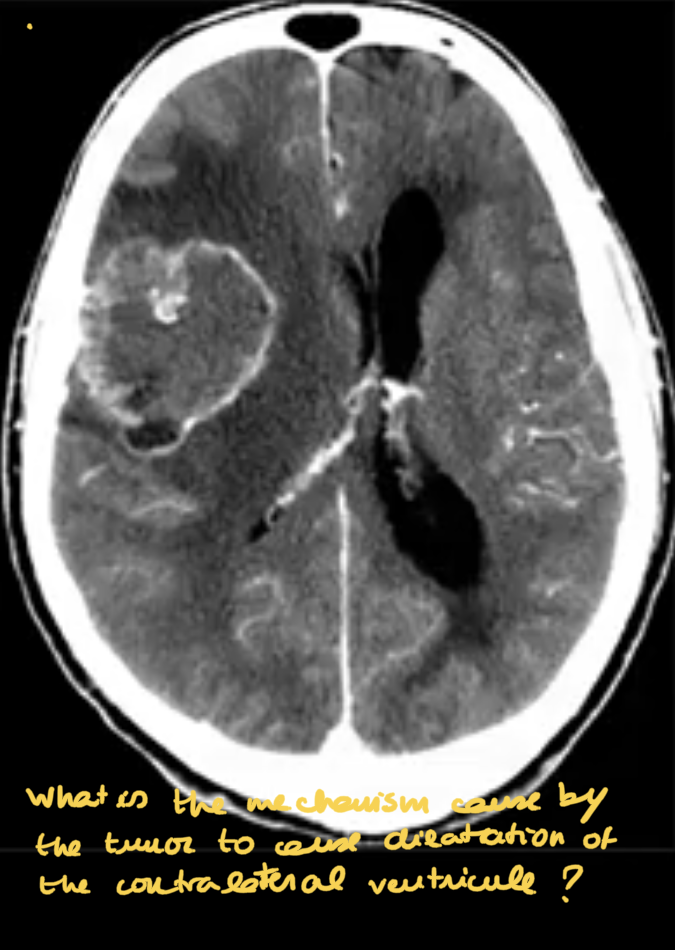

OBSTRUTIVE HYDROCEPHALUS

OBSTRUCTIVE COMMUNICATING HYDROCEPHALUS:

-causes?